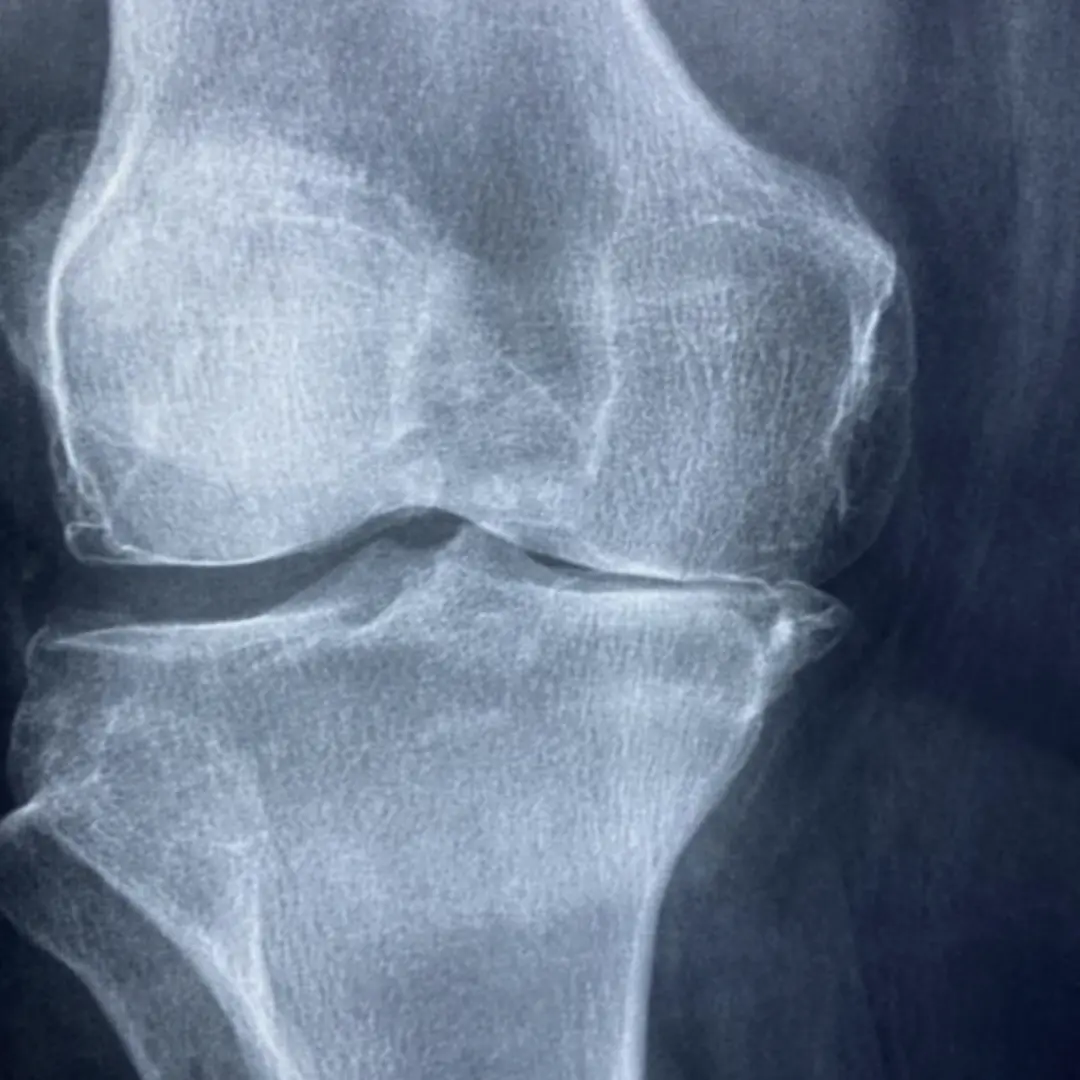

연골은 관절에서 뼈와 뼈가 직접 부딪히는 것을 막아주고, 충격을 흡수하며, 부드러운 움직임을 가능하게 하는 쿠션 역할을 합니다. 이 연골은 콘드로이틴과 함께 글루코사민을 통해 건강하게 유지될 수 있어요. 하지만 나이가 들거나, 과체중, 과도한 운동 등으로 인해 연골이 손상되거나 글루코사민 생성 능력이 떨어지면 연골이 닳아 없어지고 탄력을 잃게 됩니다. 이는 결국 관절 통증과 염증을 유발하는 퇴행성 관절염으로 이어질 수 있어요.

- 특히 퇴행성 관절염으로 인한 통증과 뻣뻣함을 개선하는 데 유효할 수 있습니다.

- 나이가 들거나 관절 손상이 발생하면 연골을 분해하는 효소들이 활성화될 수 있습니다. 글루코사민은 이러한 효소들의 활성을 억제하여 연골 손상 속도를 늦추는 데 기여할 수 있습니다.

- 가장 직접적인 도움을 받을 수 있는 대상입니다. 연골이 닳아 통증과 염증을 느끼는 분들에게 글루코사민은 연골 구성 성분을 보충하고 염증을 완화하여 통증 감소와 관절 기능 개선에 기여할 수 있습니다.